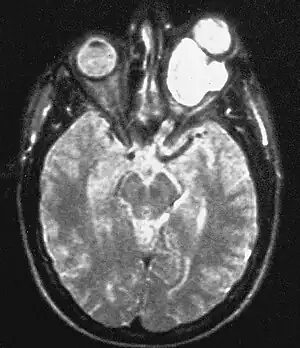

Magnetic resonance image of a large retrobulbar optic nerve tumor causing massive proptosis

Optic nerve gliomas are diagnosed using magnetic resonance imaging (MRI) and CT scans.[6] The tumor adopts a fusiform appearance, appearing wider in the middle and tapered at the ends.[6] Enlargement of the optic nerve along with a downward kink in the mid-orbit is usually observed.[6] While CT scans allow for optic nerve evaluation, MRI allows for intracranial evaluation to observe if the tumor has extended to other regions such as the optic chiasm & hypothalamus.[7]